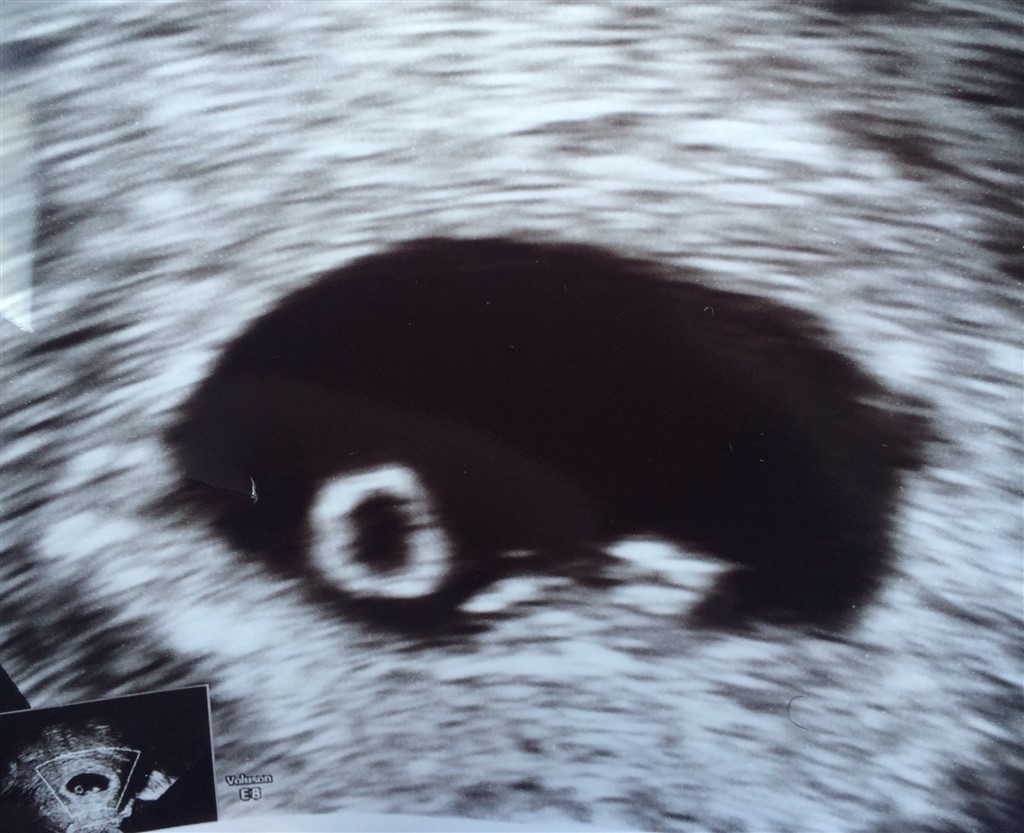

I dag valgte vi at tage en ekstra scanning i Tyskland , for at få sikkerhed om hjerteslag .

men det var du skønt at få bekræftet liv .. Ca 7+0 anslog de det til at være ..

Første billede er fra scanning for et par uger siden , andet er fra i dag . Tydelig udvikling

Møde vores lille spunk